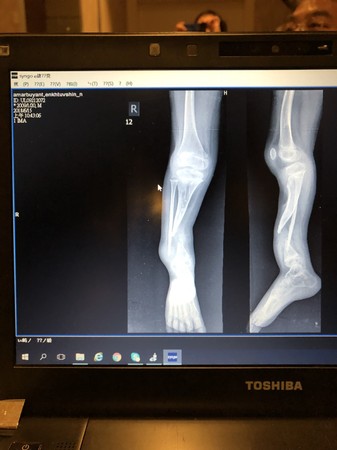

▲男童右腳腓骨和脛骨斷裂,進行手術釘鋼釘時釘錯位置發生感染,造成右腳比左腳短了10公分。

員榮醫院家醫科主任黎雨青說,阿莫只不過是骨折,卻因此讓他的童年沉浸在無法走路的陰影中。阿默在4個月時摔斷腿,當時醫生只用木板固定,一直都無法走路的阿默,9個月大時又因右腳腓骨和脛骨斷裂,進行手術釘鋼釘時釘錯位置發生感染,右腳沒有小腿骨,造成右腳比左腳短了10公分,無法正常行走,成為長短腳。

由於阿默右小腿是屬「右側脛腓骨骨折術後合併骨不癒合」,要先做開放性復位併鋼釘固定術與骨移植術,需要來台接受手術,傷口復原大概需6個月到1年左右。